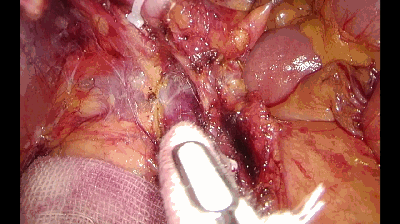

保护指引作用

直肠手术中,拓展开内侧的Toldt间隙后,把小纱布放在输尿管和生殖血管之上,可以在切开乙状结肠左侧粘连时,避免损伤上述组织器官。